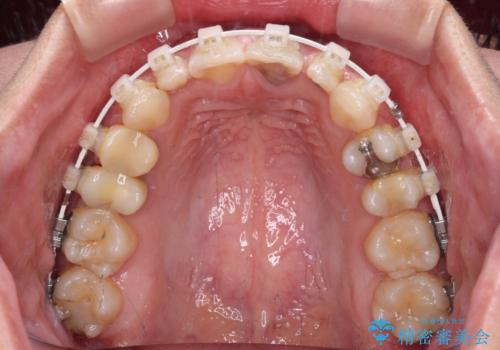

- 矯正装置

- 審美装置

矯正治療は、小臼歯1本分を歯列に納めないいけない状態であったため、表側のワイヤー装置にて行うこととしました。